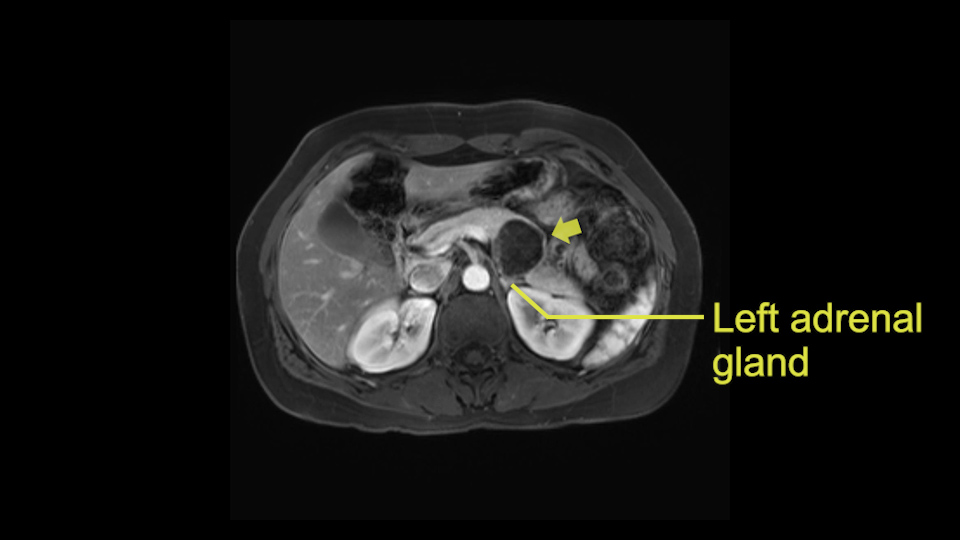

Tumor proximity to left adrenal gland

The lesion also is quite posterior. While the plane between the cyst and the left adrenal gland is often preserved, we do have to pay attention here so that we remain in the right plane and maintain our margin here. Occasionally in these cases, en bloc adrenalectomy needs to be performed.

Sometimes with even benign lesions of the spleen you can have quite a lot of inflammation in the retroperitoneum and so I do think about and wonder whether I will have some difficulty in the retroperitoneum and I usually look at the scan for that purpose. It looks like there is no inflammation in the retroperitoneum. It does look very close to the patient’s left adrenal gland but knowing the planes and suspecting that there isn’t any active inflammation, this should be able to come off the left adrenal gland without any difficulty. But obviously prepared to take some of the left adrenal if that’s necessary in this procedure. So those are my procedure-specific slowing down moments in a distal pancreatectomy when I’m considering a laparoscopic approach. I think the patient-specific slowing down moments in this particular case I have discussed with the procedure-specific moments. I don’t really see any other issue or that I have to be careful of or consider.

So first, I'll show you the scan. Here's the traditional view, where you see the cyst, which is in the body of the pancreas. And you see over here, it's got a quite thick wall. And going a little bit back also, here you see a septation which is very important, because I think a septation is what separates this from, for instance, the pseudocyst of the pancreatitis. And also the location of the cyst you see here, abutting the adrenal gland and going down a bit more, it's also quite close to a bowel loop. So when thinking about this cyst: female, the location in the body of the pancreas, thick wall, septation, and as you can read in history, it was basically asymptomatic, so no signs of pancreatitis. So, this probably all points towards a mucinous cystic neoplasm.